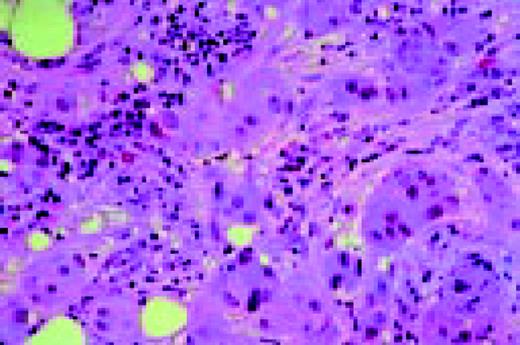

Slide E29

Refractory Anemia with excess blasts in transformation (RAEBT). Several blasts with nucleoli as well as abnormal red cells and granulocytes are seen in this field.FIG125